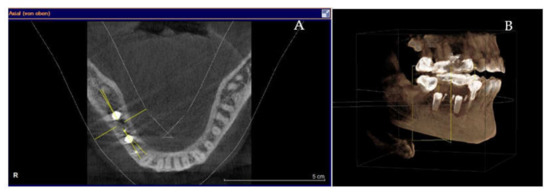

Clinical and CBCT aspects of patient from the test group, describing the stages of S-GBR technique and implant-prosthetic stage, are presented in Figure 1, Figure 2, Figure 3, Figure 4, Figure 5, Figure 6, Figure 7, Figure 8, Figure 9, Figure 10 and Figure 11. CBCT exam allows the evaluation of the horizontal alveolar bone defect and the position of the mandibular alveolar nerf (Figure 1A,B). Figure 1C,D show cross-sectional CBCT aspects of the implant sites. Figure 2 shows the narrowed mandibular alveolar bone with horizontal resorption. Figure 3 shows the exposed buccal surface of the alveolar ridge with severe horizontal resorption, after flap opening. The inserted implants (4.5 mm diameter, 11.5 mm length) and osteosynthesis screws (45° from the occlusal plan) are shown in Figure 4A. The placement of graft (autologous bone and xenograft) and collagen membrane is shown in Figure 4B. Figure 5A shows tension-free sutures, due to periosteal incisions alveolar ridge. Figure 5B shows clinical aspect at 7 months after surgery, with gingival tissue adherent on the reconstructed alveolar ridge. Figure 6 shows OPG aspect at follow-up of 7 months, with osseointegration of the dental implants. Figure 7A shows clinical aspect before osteosynthesis screws removal. Figure 7B shows clinical aspect after osteosynthesis screws removal. Figure 8A shows healthy peri-implant soft tissues. Figure 8B shows repositioning key for perfect position of abutments. Figure 10A,B show clinical aspects of implant-supported prosthetic restoration. Figure 11A,B show CBCT aspects of Osseo integrated dental implants at 24 months follow-up.

(A,B) 7-months follow-up of S-GBR surgery. (A) CBCT shows 2 mm bone around implants. (B) CBCT shows reduced bone resorption in the coronal area of implants.

Figure 11.

(A,B) CBCT aspects (cross-sectional) of osseointegrated implants at 24-months follow-up.